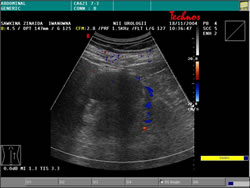

УЗИ: |

|

Динамическая

нефросцинтиграфия: |

Секреторно

– эвакуаторная функция левой почки – удовлетворительная,

правой почки снижена на 42 %. |